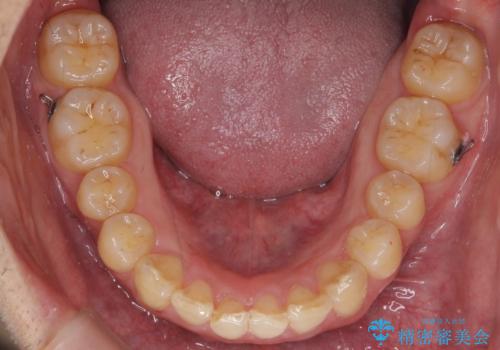

出っ歯を治したい 深いかみあわせ インビザラインで治療

下顎は歯列を拡大して並べました。

また、過蓋咬合(深いかみ合わせ)で食いしばりがきつく、歯の移動には大変時間がかかりました。

食いしばりがきついかたについては、長時間マウスピースをはめると奥歯が咬まずに前歯に負担がかかる場合があります。今回は使用時間を短くしたり、下の歯並びを早めにプレートタイプリテーナーに置き換えるような工夫を行い、治療を行いました。